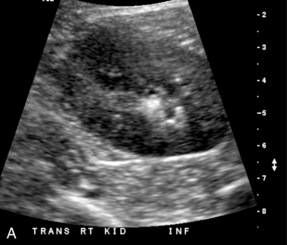

Другой метод допплерографии, помогающий оценить обструкцию мочевыводящих путей, можно провести внутри мочевого пузыря. В случаях с подозрением на почечную обструкцию ультразвуковая оценка струи мочеточника должна быть компонентом ультразвукового исследования почек ( рис. 9-6 ). Хотя поступление мочи в мочевой пузырь не синхронно, обнаружение трех и более струй мочеточника при допплерографии с одной стороны без единого импульса потока с контралатеральной стороны предполагает обструкцию непульсирующего мочеточника.

РИСУНОК 9-6. Нормальная струя мочеточника. Поперечное цветное допплеровское изображение показывает линейную «струю» цвета, выступающую в просвет мочевого пузыря. Это представляет собой быстрый поток мочи в мочевой пузырь вследствие перистальтики мочеточника.